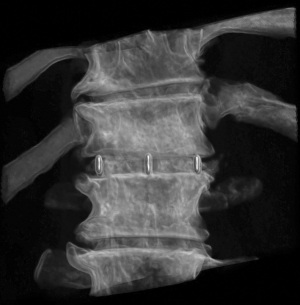

A 74-year-old male presented with a 12-month history of progressive low back pain (VAS 8/10) with an inability to stand for more than 10 minutes or participate in recreational activities. No neurologic deficit was revealed on initial examination, comorbidities included hypertension and prior history of tobacco use. Preoperative CT thoracolumbar scan demonstrated multilevel degenerative disc disease (DDD) most marked at T12-L1 with a degenerative grade I spondylolisthesis at L3-4 (Figure 6). Isotope Tc99m bone scan coregistered with CT showed radiotracer uptake mainly at T12-L1 disc level and lesser extent at L3-4 disc and L5-S1 facet joints. The patient was unresponsive to opiate analgesia, CT guided facet joint or transforaminal epidural nerve root injections. The patient underwent a left retropleural transdiaphragmatic T12-L1 LIF with an interbody cage (8×18×45 mm3, zero degree, CoRoent XL-T). EBL was less than 50 mL. A 24 gauge intercostal drain was placed intraoperatively and removed 24 hours postoperatively. Postoperative CT demonstrated satisfactory prosthesis placement at T12-L1. The patient was discharged to home on day 5. He ceased all analgesia and returned to normal work duties 5 weeks postoperatively. A solid fusion was confirmed on CT at 12 months (Figure 7). The patient reported improvements in low back pain (VAS 8/10 to 2/10), ODI (38 to 20), PCS (33 to 40) and MCS (46 to 52) at 24 month follow-up.